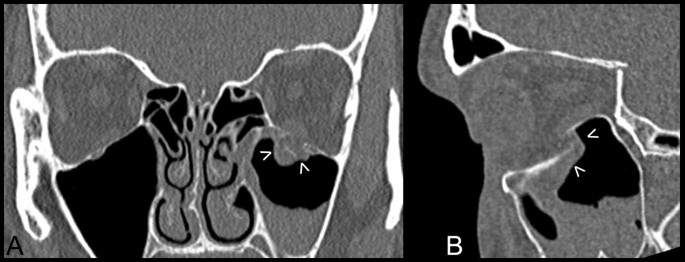

After clinical diagnosis, (Figure 2A, B) a consultation by an ophthalmologist (including binocular single vision test) (Figure 2C) and in case of need a neurosurgeon, patients were qualified to patient specific treatment either by titanium mesh (Synthes, Zuchwil, Switzerland) shaped on a 3D printed model of a mirrored intact orbit [7, 15] or by individually manufactured UHMW-PE implant.

Results of treatment. A – computerized tomography in sagittal view: titanium mesh deformated during intra-orbital maneuvres in primary surgery (asterisk); its deepest located part hurts the inferior rectus muscle. B – downgaze significantly limited in the left eye; C – result of binocular single vision loss test: diplopia caused by titanium mesh is mainly up- and downgaze. D - computerized tomography in sagittal view after corrective surgery and exchange of the implant to stiff patient specific ultra-high molecular weight polyethylene implant: orbital floor is reconstructed (arrow) and inferior rectus muscle is free. E – normal eye globe motility: full downgaze 1 month post-operationally. F - result of binocular single vision loss test: residual diplopia in upgaze/left.

Further on, patients were operated under general anaesthesia by the same surgeon (author MK) (Figure 3). Transconjunctival approach was used in all cases (Figure 3A). In the first group flat titanium 0.4 mm thick mesh was shaped preoperatively by operating surgeon(MK) on a solid individual model [Ti-Mesh] [7, 15]. In the next group previously prepared ultrahigh molecular weight polyethylene [UHMW-PE] [16] implants were used to reconstruct affected lower or lower and medial wall of the orbit. The correctness of position of implant during operation was controlled by checking implant alignment in previously designed reference areas (usually lower orbital rim anteriorly and orbital process of palatal bone posteriorly). In both groups the anatomical orbital wall reconstruction were obtained. Computerized tomography was performed in the first week after surgery (Figure 2D) to evaluate the quality of the reconstruction and the condition of surrounding tissues to exclude any complications. Binocular single vision was again evaluated post-operationally in 1 month and 6 months later (Figure 2F).